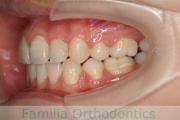

No.21V-042

- 側方偏位

- 叢生

- 39歳

- 女性

- 抜歯部位

- 上:

- 44

- 下:

- 1|8

- 主な使用装置:

- FEA

- 治療にかかった費用:

- 90万円

八重歯を治したい、とのことで来院されました。アゴのズレが大きいこと、親知らずに下の奥歯が一部食い込まれていて保存に不安があったこと、から上の左右小臼歯と下の前歯一本を抜歯してマルチブラケット法を行いました。4年弱、45回程度の通院が必要でした。

上下前歯とも叢生(でこぼこ、凹凸、ガタガタ)が強く、後戻りのリスクのあるケースです。